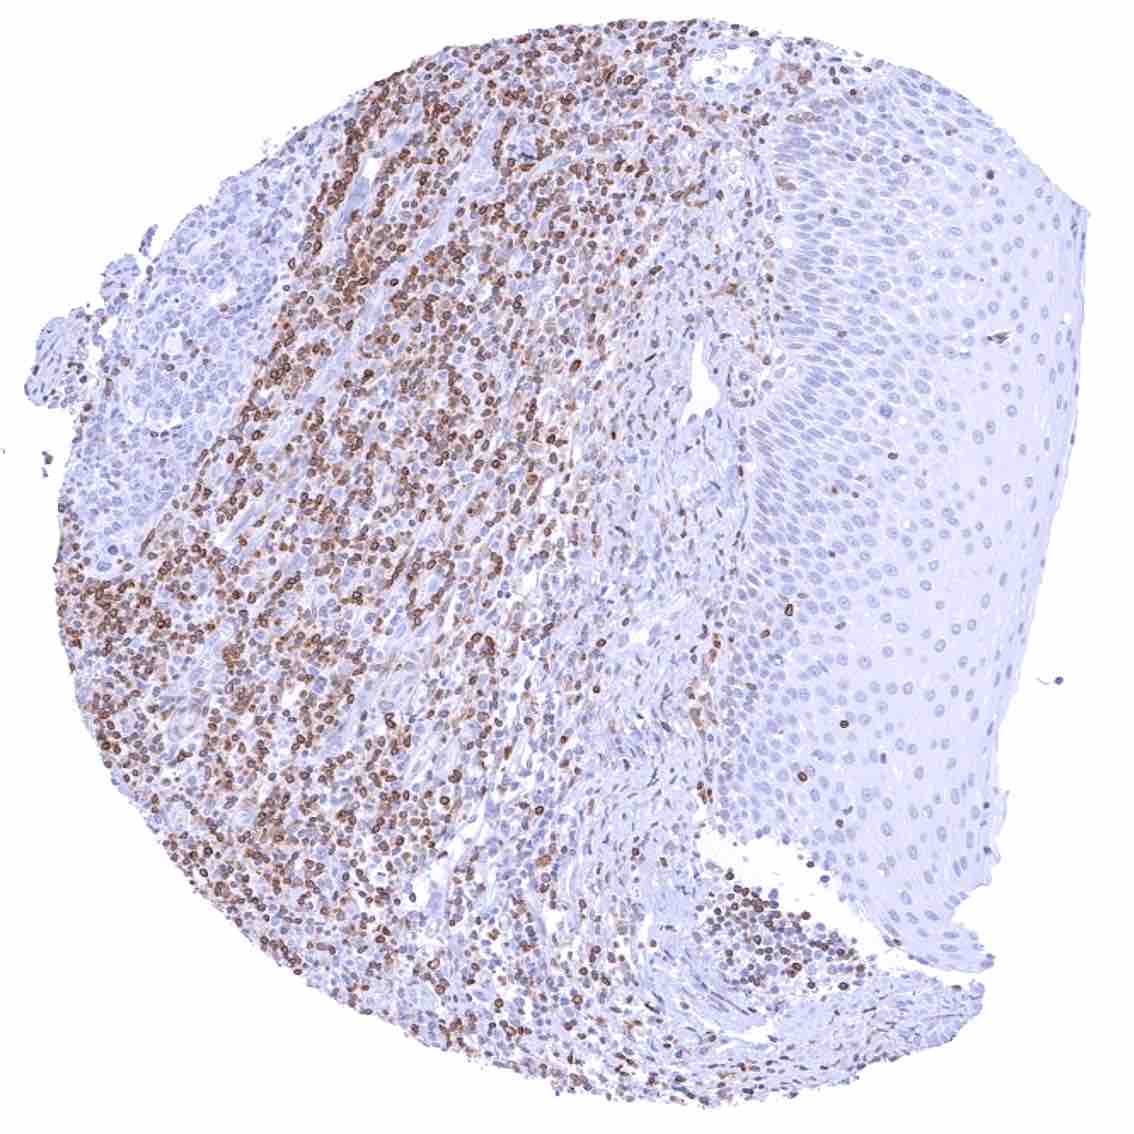

Tonsil –Strong bcl-2 positivity of large fraction of lymphocytic cells in the interfollicular area & around germinal centres. Cells in germinal centres are largely bcl-2 negative. Squamous epithelium with weak bcl-2 staining of the basal cell layer

Tonsil, surface epithelium